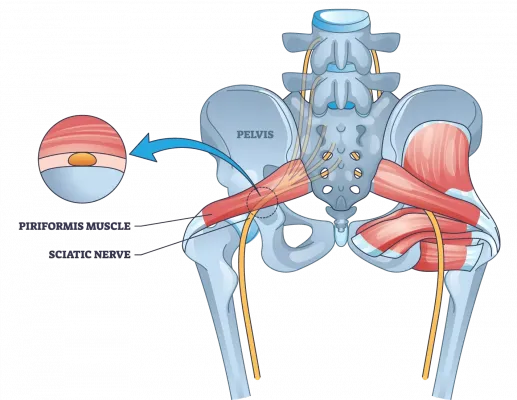

Anatómia Piriformis svalu

Piriformis je malý, plochý sval hruškovitého tvaru, ktorý sa nachádza hlboko v zadku. Leží v strede sedacej časti a priamo pod veľkým svalom gluteus maximus, ktorý poskytuje tvar a formu zadku a… Viac